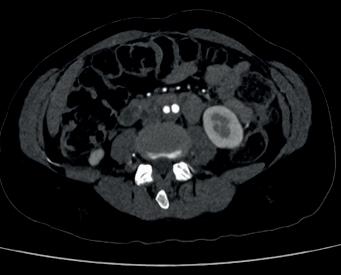

The study was a retrospective review of 66 patients with a median age of 31 who underwent UAE for uncontrolled postpartum haemorrhage at a single, high-volume medical centre between 2014–2022. UAE successfully controlled postpartum haemorrhaging in 62 of the 66 patients (94%). Four patients required hysterectomies to stop the bleeding, all of whom lost at least 2,400ml blood prior to presentation for UAE and showed symptoms of diffuse intravascular coagulopathy, a clotting abnormality that can happen after large-volume haemorrhage due to rapid consumption of clotting factors.

Postpartum haemorrhage is a rare, but potentially deadly complication of childbirth. To stop it, obstetricians will initially use conservative approaches to replace the lost blood or to promote clotting. If these measures are insufficient, hysterectomy is usually performed. Alternatively, interventional radiologists can be brought in to perform UAE, injecting tiny particles into the arteries that supply blood to the uterus using fluoroscopic imaging guidance. Once placed in the arteries, the particles temporarily block blood flow to stem uterine bleeding.